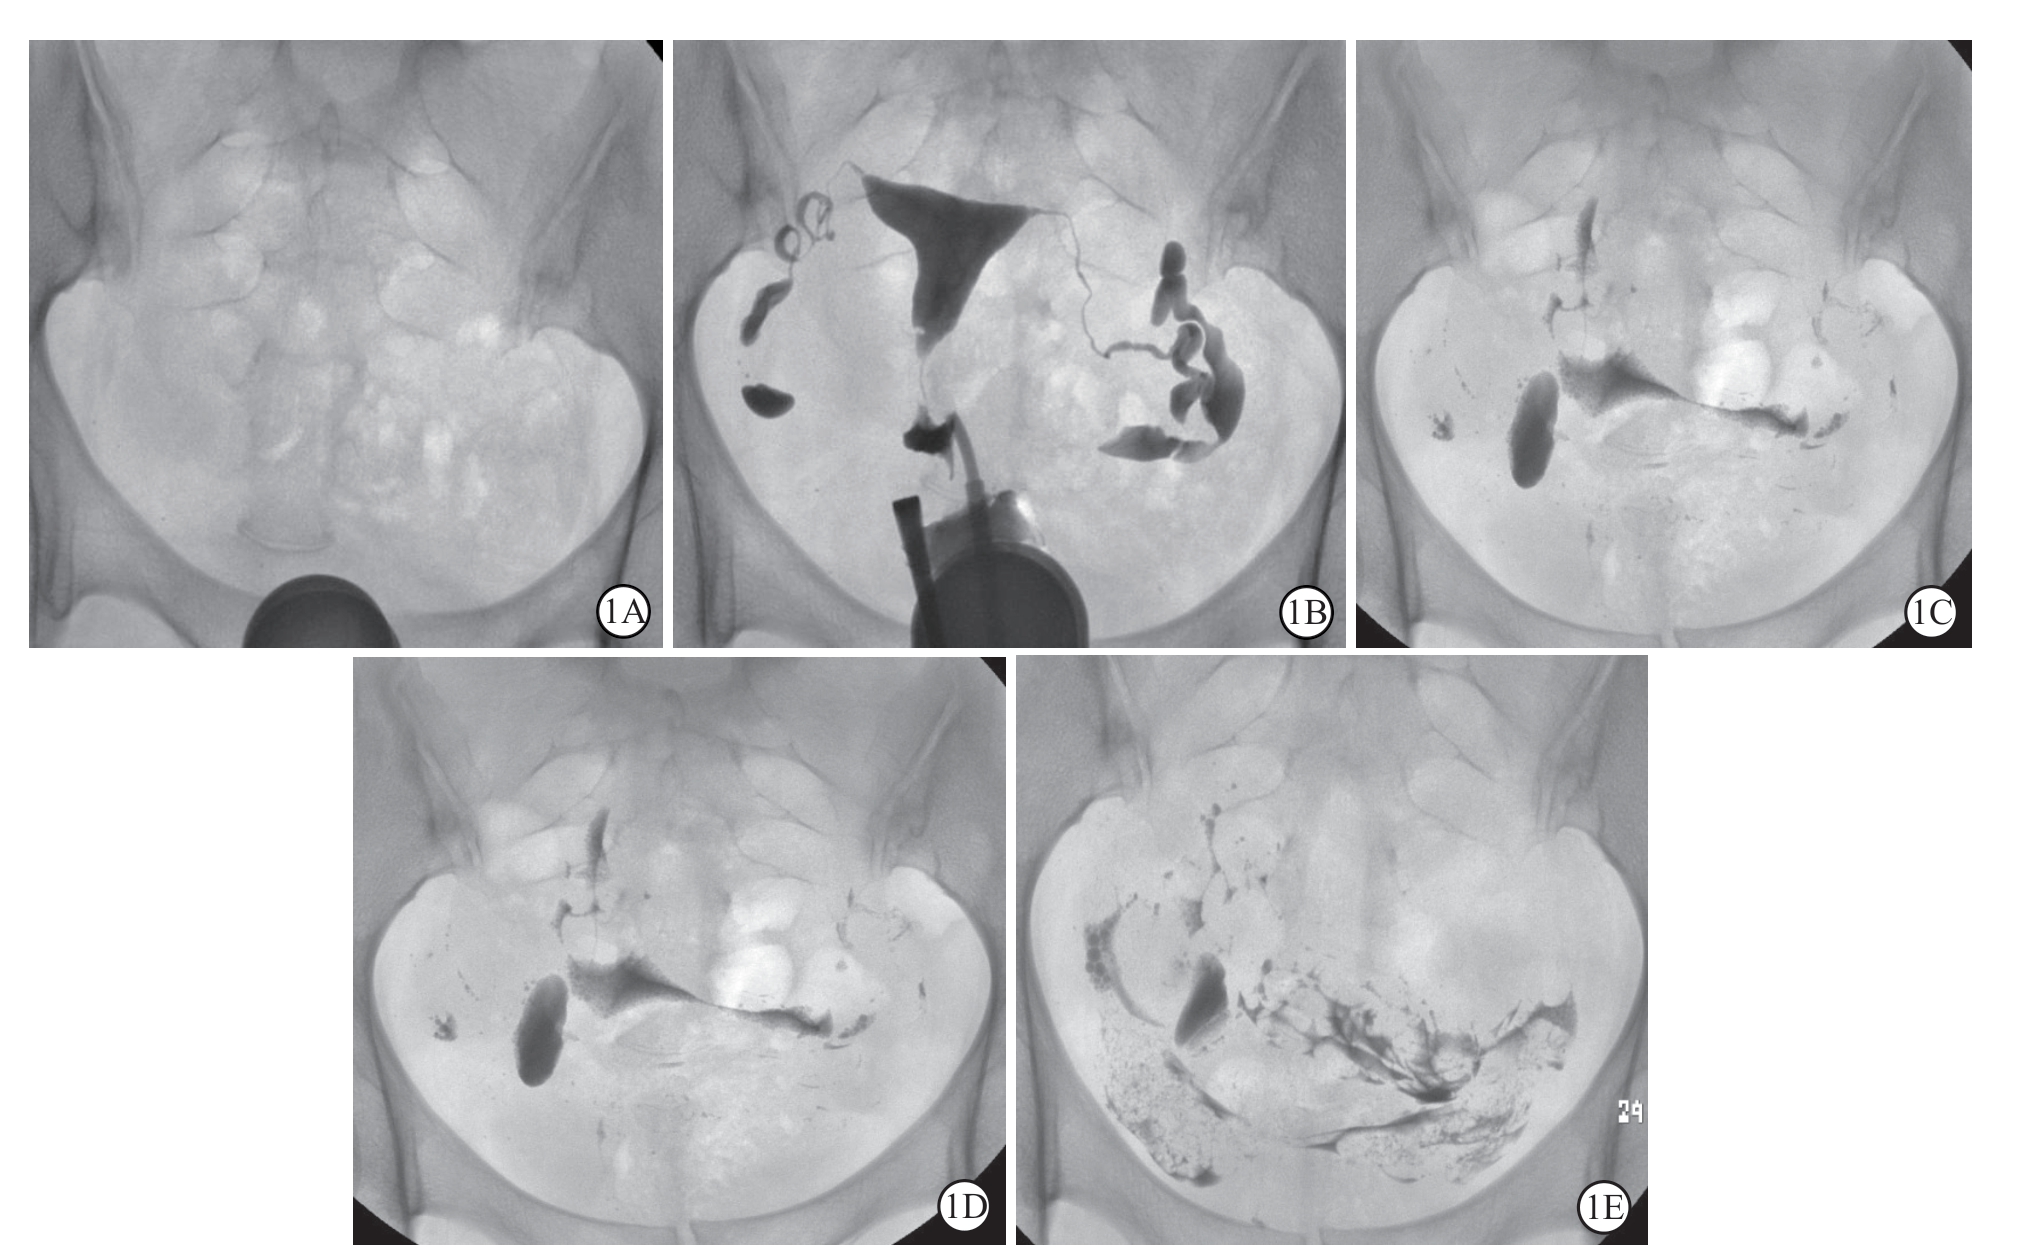

图1 超液化碘油子宫输卵管造影 1A:定位片;1B:充盈期图像显示子宫腔和输卵管;1C:3 h延迟片;1D:6 h延迟片;1E:24 h延迟片。